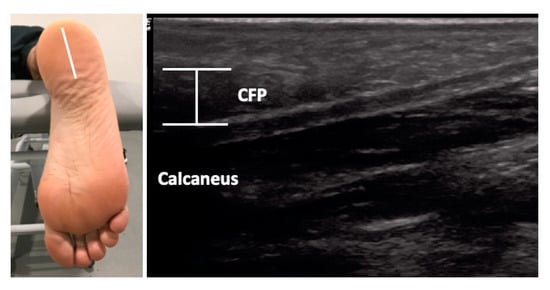

The USI assessments were carried out using a high-quality system LogiQ P7 (GE Healthcare; UK) with a 4 to 13 MHz linear transducer (L6-12 RS type, 38 mm footprint). All ultrasound evaluations of the PF were carried out in a supine position with the transducer placed in direct contact with the skin. The PF was scanned in a longitudinal view in all locations. Firstly, for the enthesis at the calcaneus location, the transducer was placed on the line between the medial calcaneal tubercle and the second toe over the PF (Figure 1, A). Secondly, for the midfoot PF assessment, the transducer was located on the same scanning line at the navicular tubercle (Figure 1, B). Thirdly, for the metatarsal region of the PF, the transducer was located on the same longitudinal line near to the second metatarsal head (Figure 1, C) [29]. For the ultrasound examination of the CFP, the subjects were placed in a prone position and the transducer was placed longitudinally at the midpoint of the heel (Figure 2) [24]. According to López et al. [30], the evaluator both flexed and extended the big toe while palpating the subject´s PF to allow accurate identification of the calcaneal tuberosity. All the examinations were carried out by a physiotherapist (P.M.L.) with more than 5 years of experience in ultrasonography. The final scores were collected by the mean of 3 repeated values for each measurement with the ImageJ software (Bethesda, MD, USA).

Figure 2. Ultrasound imaging thickness for the calcaneal fat pad in an individual with AT. Abbreviations: CFP, calcaneal fat pad.